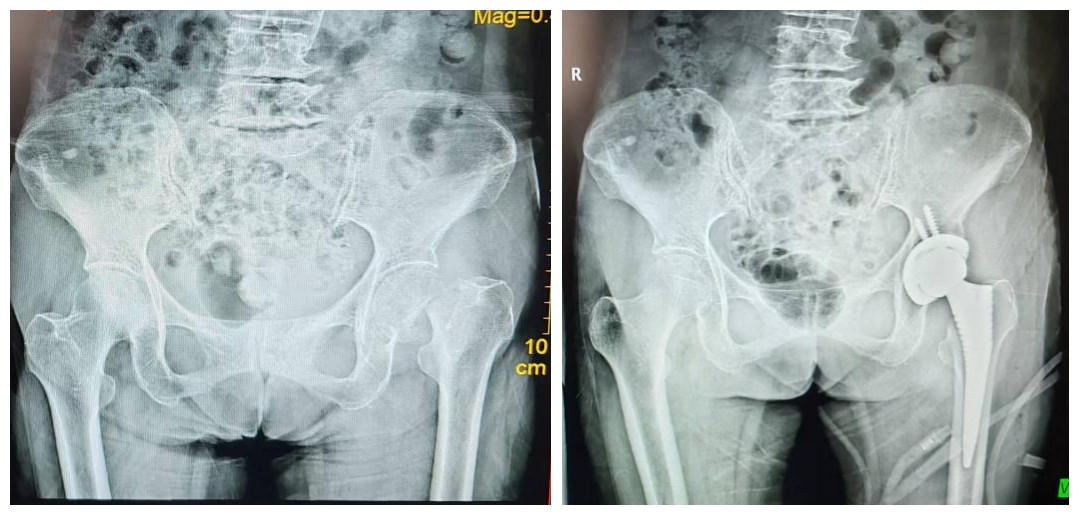

一场意外的在家摔伤,让79岁的莫阿婆陷入了“躺床望月”的困境,摔伤后阿婆无法站立,紧急送往我院拍X光片显示左侧股骨颈骨折,对于高龄老人而言,国外称作“人生最后一次骨折”,骨折不仅意味着需要长期卧床的痛苦,更潜藏着肺部感染等多种并发症的风险。近日,我院关节运动医学赵良军副院长、覃刚主任带领团队开展了医院首例侧卧位直接前方入路(Direct Anterior Approach,DAA)人工全髋关节置换术,手术从切皮、安装假体到皮肤缝合整个手术过程用时不到1小时,标志着我院在DAA微创全髋关节置换技术领域达到区内先进水平。

“当时就听到‘咔嚓’一声,之后腿就动不了,疼得直冒汗”,回忆起摔倒的瞬间,莫阿婆仍心有余悸。急诊科诊断为左侧股骨颈骨折,入住我院关节运动医学病区(骨一科),完善相关检查,考虑到阿婆年近八旬,身体状况虚弱,科室讨论决定采用国际前沿的DAA入路行全髋关节置换术,术前相关检查未见明显禁忌症后,于2025.12.31在全麻下行侧卧位DAA全髋关节置换术,整个手术过程行云流水,从皮肤切开到假体安装完毕,仅用时30多分钟,术中出血少、视野清晰,假体位置及稳定性均良好,术后6小时即可扶助行器下床活动,实现了“早下床、早康复”的终极目标,家属对手术效果赞不绝口。